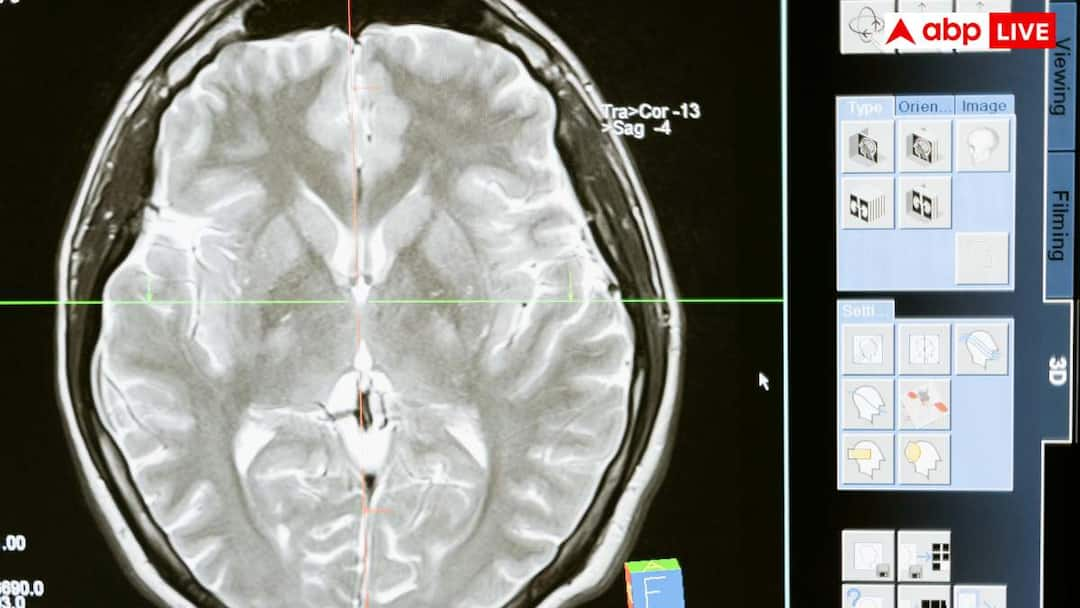

According to neurologists, when the causes of seizures in children were investigated and their brains were scanned, the main cause of seizures was found to be parasitic infection or worms present in the brain. It is important for everyone to know how parasitic infection is becoming the main cause of seizures in children.

The main cause of parasitic infection in the brain is a condition called neurocysticercosis. This is a condition in which this problem occurs due to the eggs of pig tapeworm, which we also call pork tapeworm, lay in our brain. These eggs can be found anywhere, such as in soil, dirty food or among leafy vegetables. By consuming these, these eggs go directly to the brain through our blood and get deposited there. The thing to note is that these are not insects, but their eggs.

The biggest reason for seizures in neurocysticercosis is that the brain makes many reactions to avoid these eggs. When these eggs reach the brain, our body creates swelling around them, so that external threats can be stopped at one place. Due to this swelling, there is a disturbance in the electrical signals of our brain cells, which causes seizures. As this egg starts rotting in the brain, many types of problems start occurring, which include headaches and seizures.